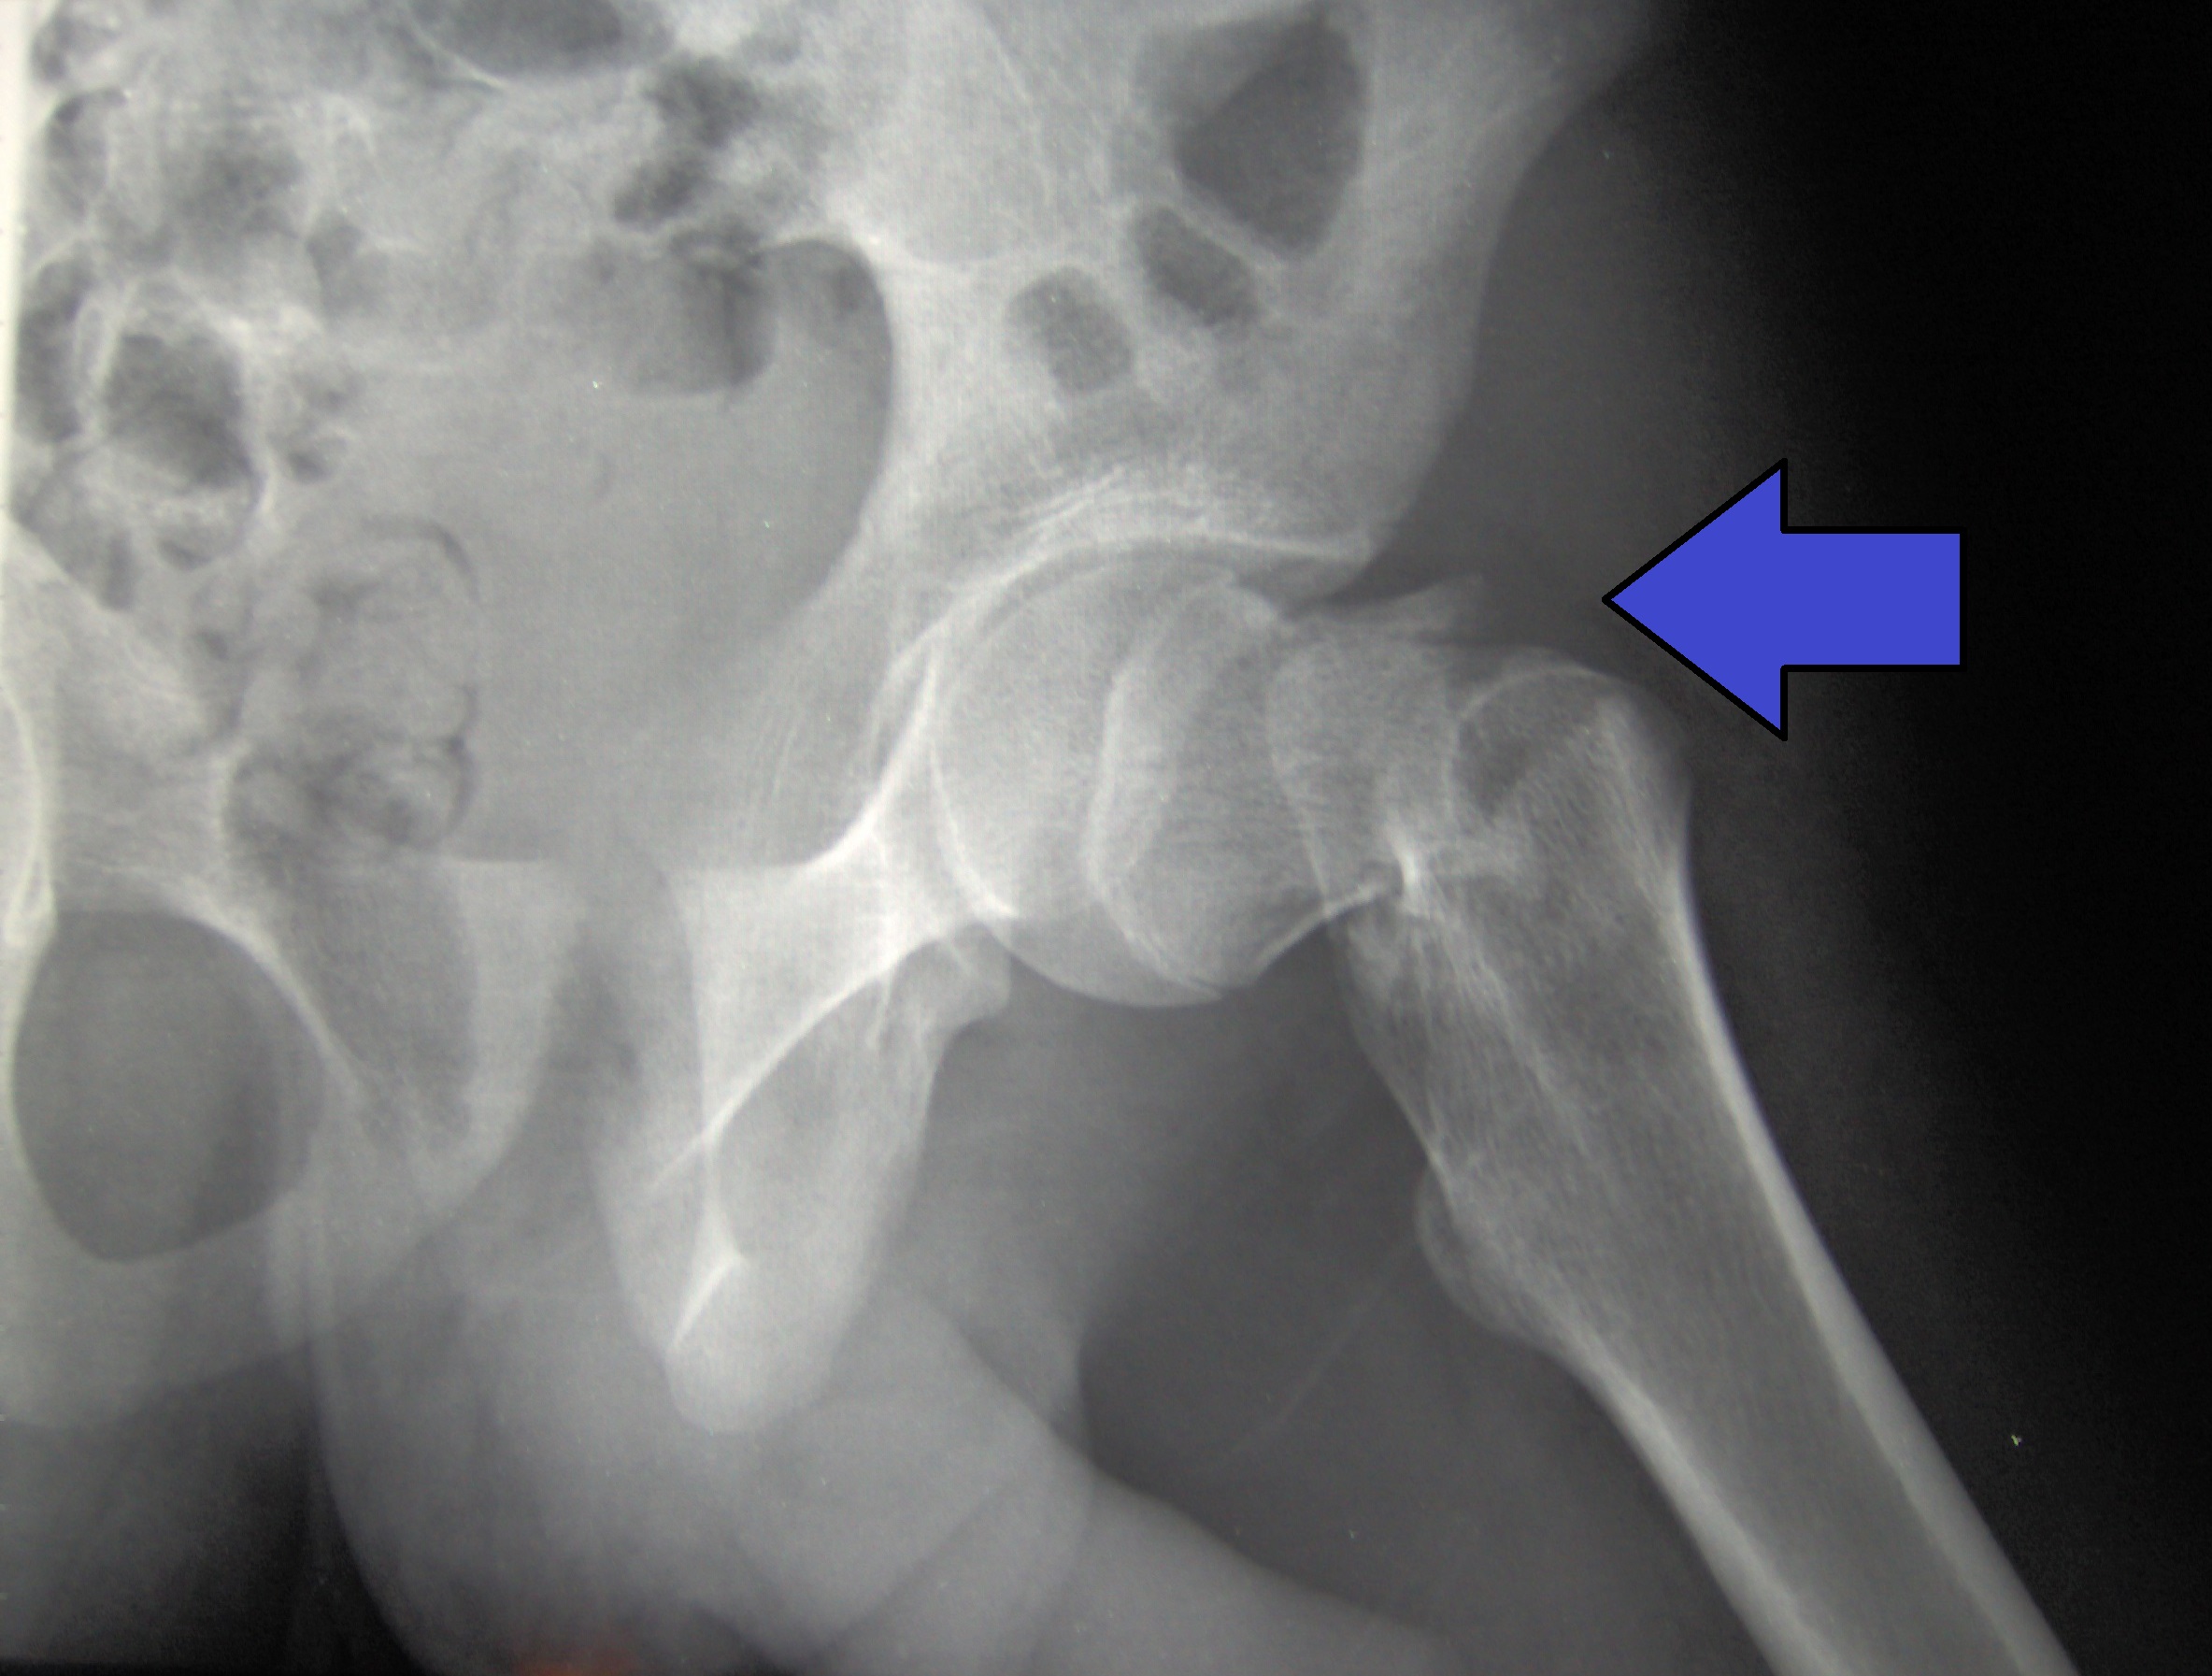

En un ensayo clínico con más de 20.000 adultos de 60 a 89 años, el agregado de una dosis mensual de 60.000 UI de vitamina D durante 5 años no redujo la incidencia de fracturas totales ni las de cadera en comparación con el placebo. The Lancet Diabetes & Endocrinology, 31 de marzo de 2023.